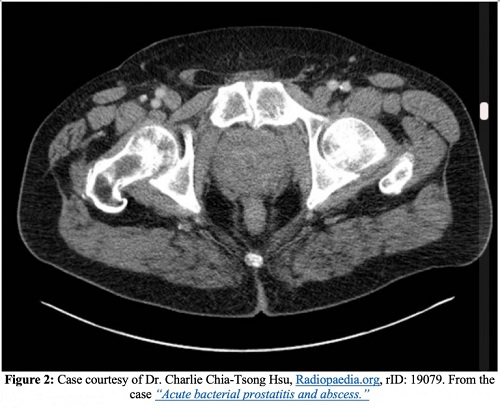

La tomodensitométrie avec et sans contraste intraveineux peut être utile pour déterminer l’étendue de la maladie, c’est-à-dire en relation avec la propagation nécrosante, et constitue la modalité d’imagerie privilégiée pour évaluer les abcès emphysémateux de la prostate.

Outre l’endocardite, l’épididymite, la propagation de l’infection aux espaces osseux ou articulaires et le développement d’une prostatite chronique, l’une des complications les plus graves de la prostatite aiguë est un abcès de la prostate. Sur les images tomodensitométriques, les abcès de la prostate apparaissent comme des collections de liquide non rehaussées. Les abcès prostatiques apparaîtront sous forme de zones anéchoïques ou hypoéchogènes à l’échographie transrectale.